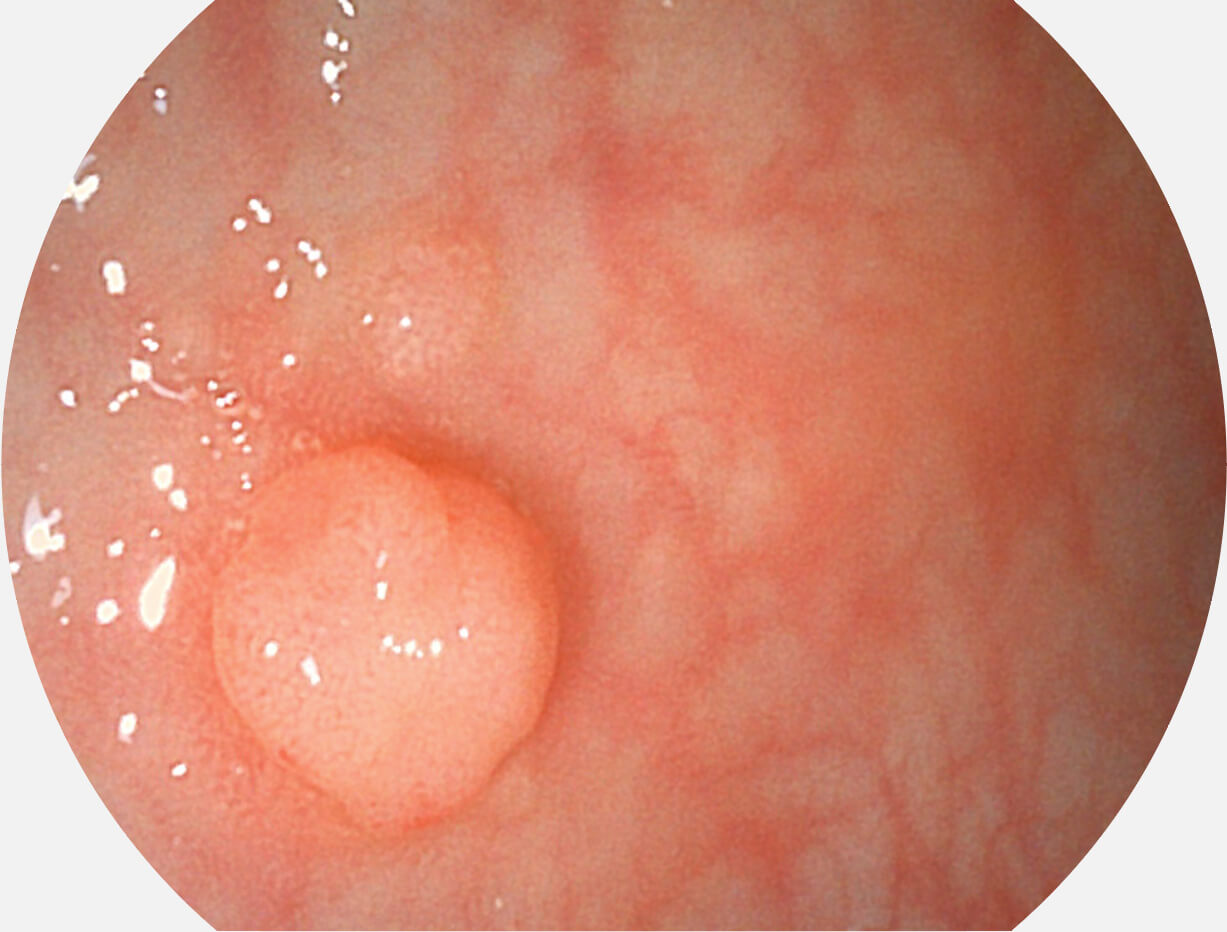

聚谱成像技术

Spectral Focused lmaging, SFI

图像具有高亮度、高黏膜血管颜色对比度的特点,且不改变粘液、食物残渣、粪便的基本颜色,可在中远景下进行观察,助力消化道早期疾病的诊断。

• 白光图像 SFI图像